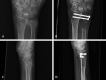

The distal radioulnar joint (DRUJ), the articulation between the sigmoid notch of the radius and the distal ulna, plays a pivotal role in stability and load bearing and allows for pronation and supination of the forearm. Osteoarthritis (OA) of the DRUJ commonly occurs due to distal radius trauma but may also be the result of conditions such as joint instability, septic arthritis, or primary OA. It is initially managed with conservative therapy, but surgery is often considered when nonoperative methods fail. The surgical approaches available to treat this pathology have grown over the years. The procedures have generally favorable outcomes, each with their own unique complications and considerations. This paper comprises a review of the outcomes and complications for the different procedures commonly used to surgically treat DRUJ OA.